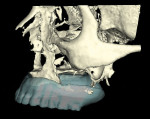

Ten radiopaque markers (gutta percha, Hygenic®, Coltène/Whaledent Group, www.coltene.com) were placed in the maxillary complete denture to prepare the denture for a specific guided- surgery protocol (NobelClinician™ Software, Nobel Biocare USA, LLC, www.nobelbiocare.com).23-30 This protocol uses a dual cone beam computed tomography (CBCT) scan procedure. The first CBCT scan (i-CAT®, Imaging Sciences International Inc., www.imagingsciences.com) was taken with the patient’s dentures in place, and a second CBCT scan was taken of the maxillary complete denture alone. The two scans were exported in Digital Imaging and Communications in Medicine (DICOM) format and loaded into the guided-surgery software, where a 3-dimensional (3-D) virtual working model of the patient was generated (Figure 4 through Figure 7) to enable virtual implant planning to be performed. Because the patient’s denture contained the approved esthetic arrangement of the teeth, the implants could be placed virtually in the most prosthetically favorable position.

The finalized virtual implant plan (Figure 8 through Figure 12) consisted of two 10-mm implants and one 13-mm implant in the maxillary anterior region, which engaged the cortical bone at the inferior border of the nasal cavity. The plan called for two 18-mm implants to be placed in the pterygomaxillary31,32 region at an approximately 45-degree angle to the occlusal plane. These pterygomaxillary implants would provide posterior support for the restoration and eliminate a posterior cantilever.33-36 In order to shorten the span between the three anterior and two posterior implants, three zygoma implants were planned on the pre-surgica lcomputer model to transect through the sinus cavity and engage the zygoma bone. All implants in the virtual planning were external-connection regular-platform implants (Brånemark® System, Nobel Biocare).